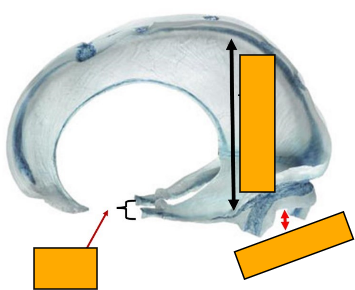

How is the cranial vault divided into compartments?

-divided into 2 continuous compartments by inward folds of the meningeal layer of dura mater

What is the tentorium cerebelli and what does it do

tent shaped fold of dura mater

divides the intracranial cavity into supratentorial and infratentorial compartments

What are the posterior, lateral and anterior attachements of the tentorium cerebelli

posterior- internal occipital protuberance and transverse sulci

lateral- superior border of the petrous part of the temporal bone

anteriorly- anterior and posterior clinoid processes

Label this image